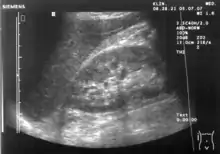

Abdominal ultrasonography (also called abdominal ultrasound imaging or abdominal sonography) is a form of medical ultrasonography (medical application of ultrasound technology) to visualise abdominal anatomical structures. It uses transmission and reflection of ultrasound waves to visualise internal organs through the abdominal wall (with the help of gel, which helps transmission of the sound waves). For this reason, the procedure is also called a transabdominal ultrasound, in contrast to endoscopic ultrasound, the latter combining ultrasound with endoscopy through visualize internal structures from within hollow organs.

Abdominal ultrasound can be used to diagnose abnormalities in various internal organs, such as the kidneys,[1] liver, gallbladder, pancreas, spleen and abdominal aorta. If Doppler ultrasonography is added, the blood flow inside blood vessels can be evaluated as well (for example, to look for renal artery stenosis). It is commonly used to examine the uterus and fetus during pregnancy; this is called obstetric ultrasonography.[2][3]